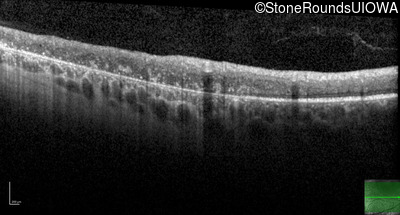

Optical Coherence Tomography - Left - 20/20 -1

Exemplar / OCT Stack